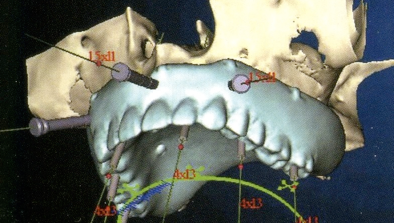

最低4本のインプラントを埋入し、それらを連結し、半日で固定式の仮歯まで入れて審美性、機能性を一日でとりもどせる革新的な治療。

1.従来インプラントは歯茎の中の骨に結合する3〜6ヶ月までは、歯をいれて噛ませることはできないと言われてきましたが、特殊な手術法によりインプラントを埋入し、4本〜6本を連結固定することにより、手術したその日からインプラントで食事を噛んでもらうことができるようになります。

3.インプラントの本数を少なくできることは、経済的も優れています。従来の治療では、無歯はでは10〜14本のインプラントを埋入していたのでそれと比較すると、かなりの治療費を削減できると考えます。